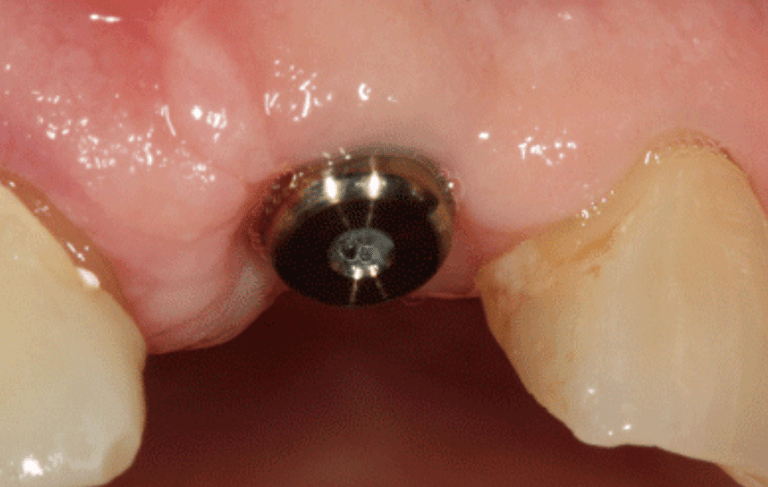

Consiste en insertar un tornillo de titanio en el hueso de la mandíbula o el maxilar, que actúa como raíz del diente y sirve de soporte para una corona, puente o prótesis dental.

Consiste en exponer los implantes después de su integración ósea y colocar los pilares que servirán de soporte para las prótesis definitivas.

Cirugía de Conexión de implantes

Colocación de un pilar provisional para mantener el espacio y la estética mientras se espera la fabricación de la prótesis definitiva.

Colocación de Pilar de Cicatrización